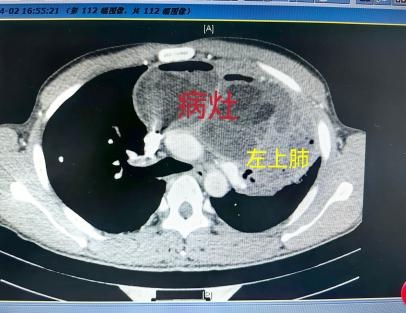

文先生的CT检查显示,他的前纵隔有个直径12cm的巨大占位。

纵隔占位考虑畸胎瘤,且肿瘤可能与左上肺的气管相通,一躺低即有少量囊液或肿瘤组织进入病人气道,造成剧咳。久而久之,造成左上肺严重感染,并通过气道影响到其他肺叶。通过多次送检,患者肺结核的指标均为阴性。针对原先抗真菌感染治疗效果不佳,专家也调整了抗感染方案。

文先生的病情稳定以后,复查胸部CT显示前纵隔肿瘤较前缩小了。